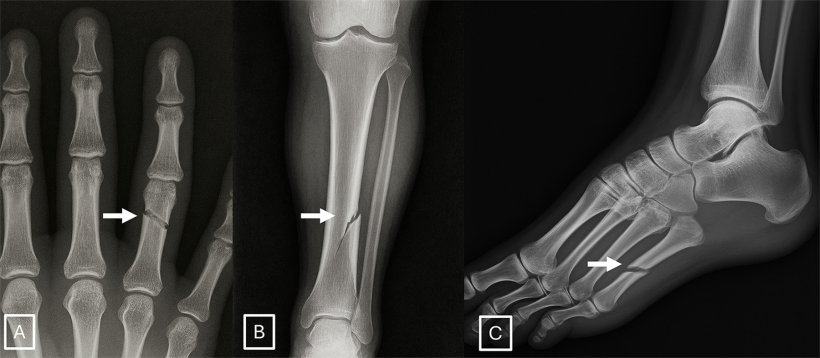

Deepfake medical images often look too perfect. Bones are overly smooth, spines unnaturally straight, lungs overly symmetrical, blood vessel patterns excessively uniform, and fractures appear unusually clean and consistent, often limited to one side of the bone

The study identified common features of synthetic X-rays. "Deepfake medical images often look too perfect,” Dr. Tordjman said. “Bones are overly smooth, spines unnaturally straight, lungs overly symmetrical, blood vessel patterns excessively uniform, and fractures appear unusually clean and consistent, often limited to one side of the bone."